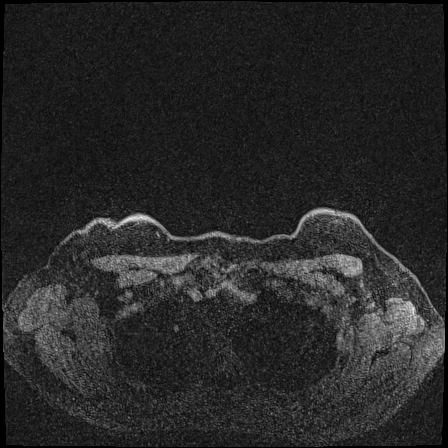

MRI images. The data used in this study are from the DUKE Breast Cancer Dataset [23], a comprehensive single-institutional retrospective collection of 3D MRI scans from over 900 patients with biopsy-confirmed invasive breast cancer at a university hospital. Each study includes a 3D MRI acquired using 1.5T or 3T scanners, from patients in the prone position. On average, each 3D scan consist of 250 2D slices (see Figure 1). For the predictive tasks, the slices are categorized into two groups: those containing breast tumors and those without. Following the approach of [15, 12], we establish a buffer zone between slices containing tumors and those that do not (highlighted in yellow in Figure 1(a)). Images within this buffer zone are excluded from analysis, and the remaining slices are labeled and used for the predictive task.

Vertical orientation. Different from magnetic field strength, which affects the entire image globally, vertical orientation is a local feature that only alters the spatial arrangement of structures within the image. This transformation does not modify the underlying tissue characteristics or signal properties but instead introduces artificial correlations that models may exploit as shortcuts.